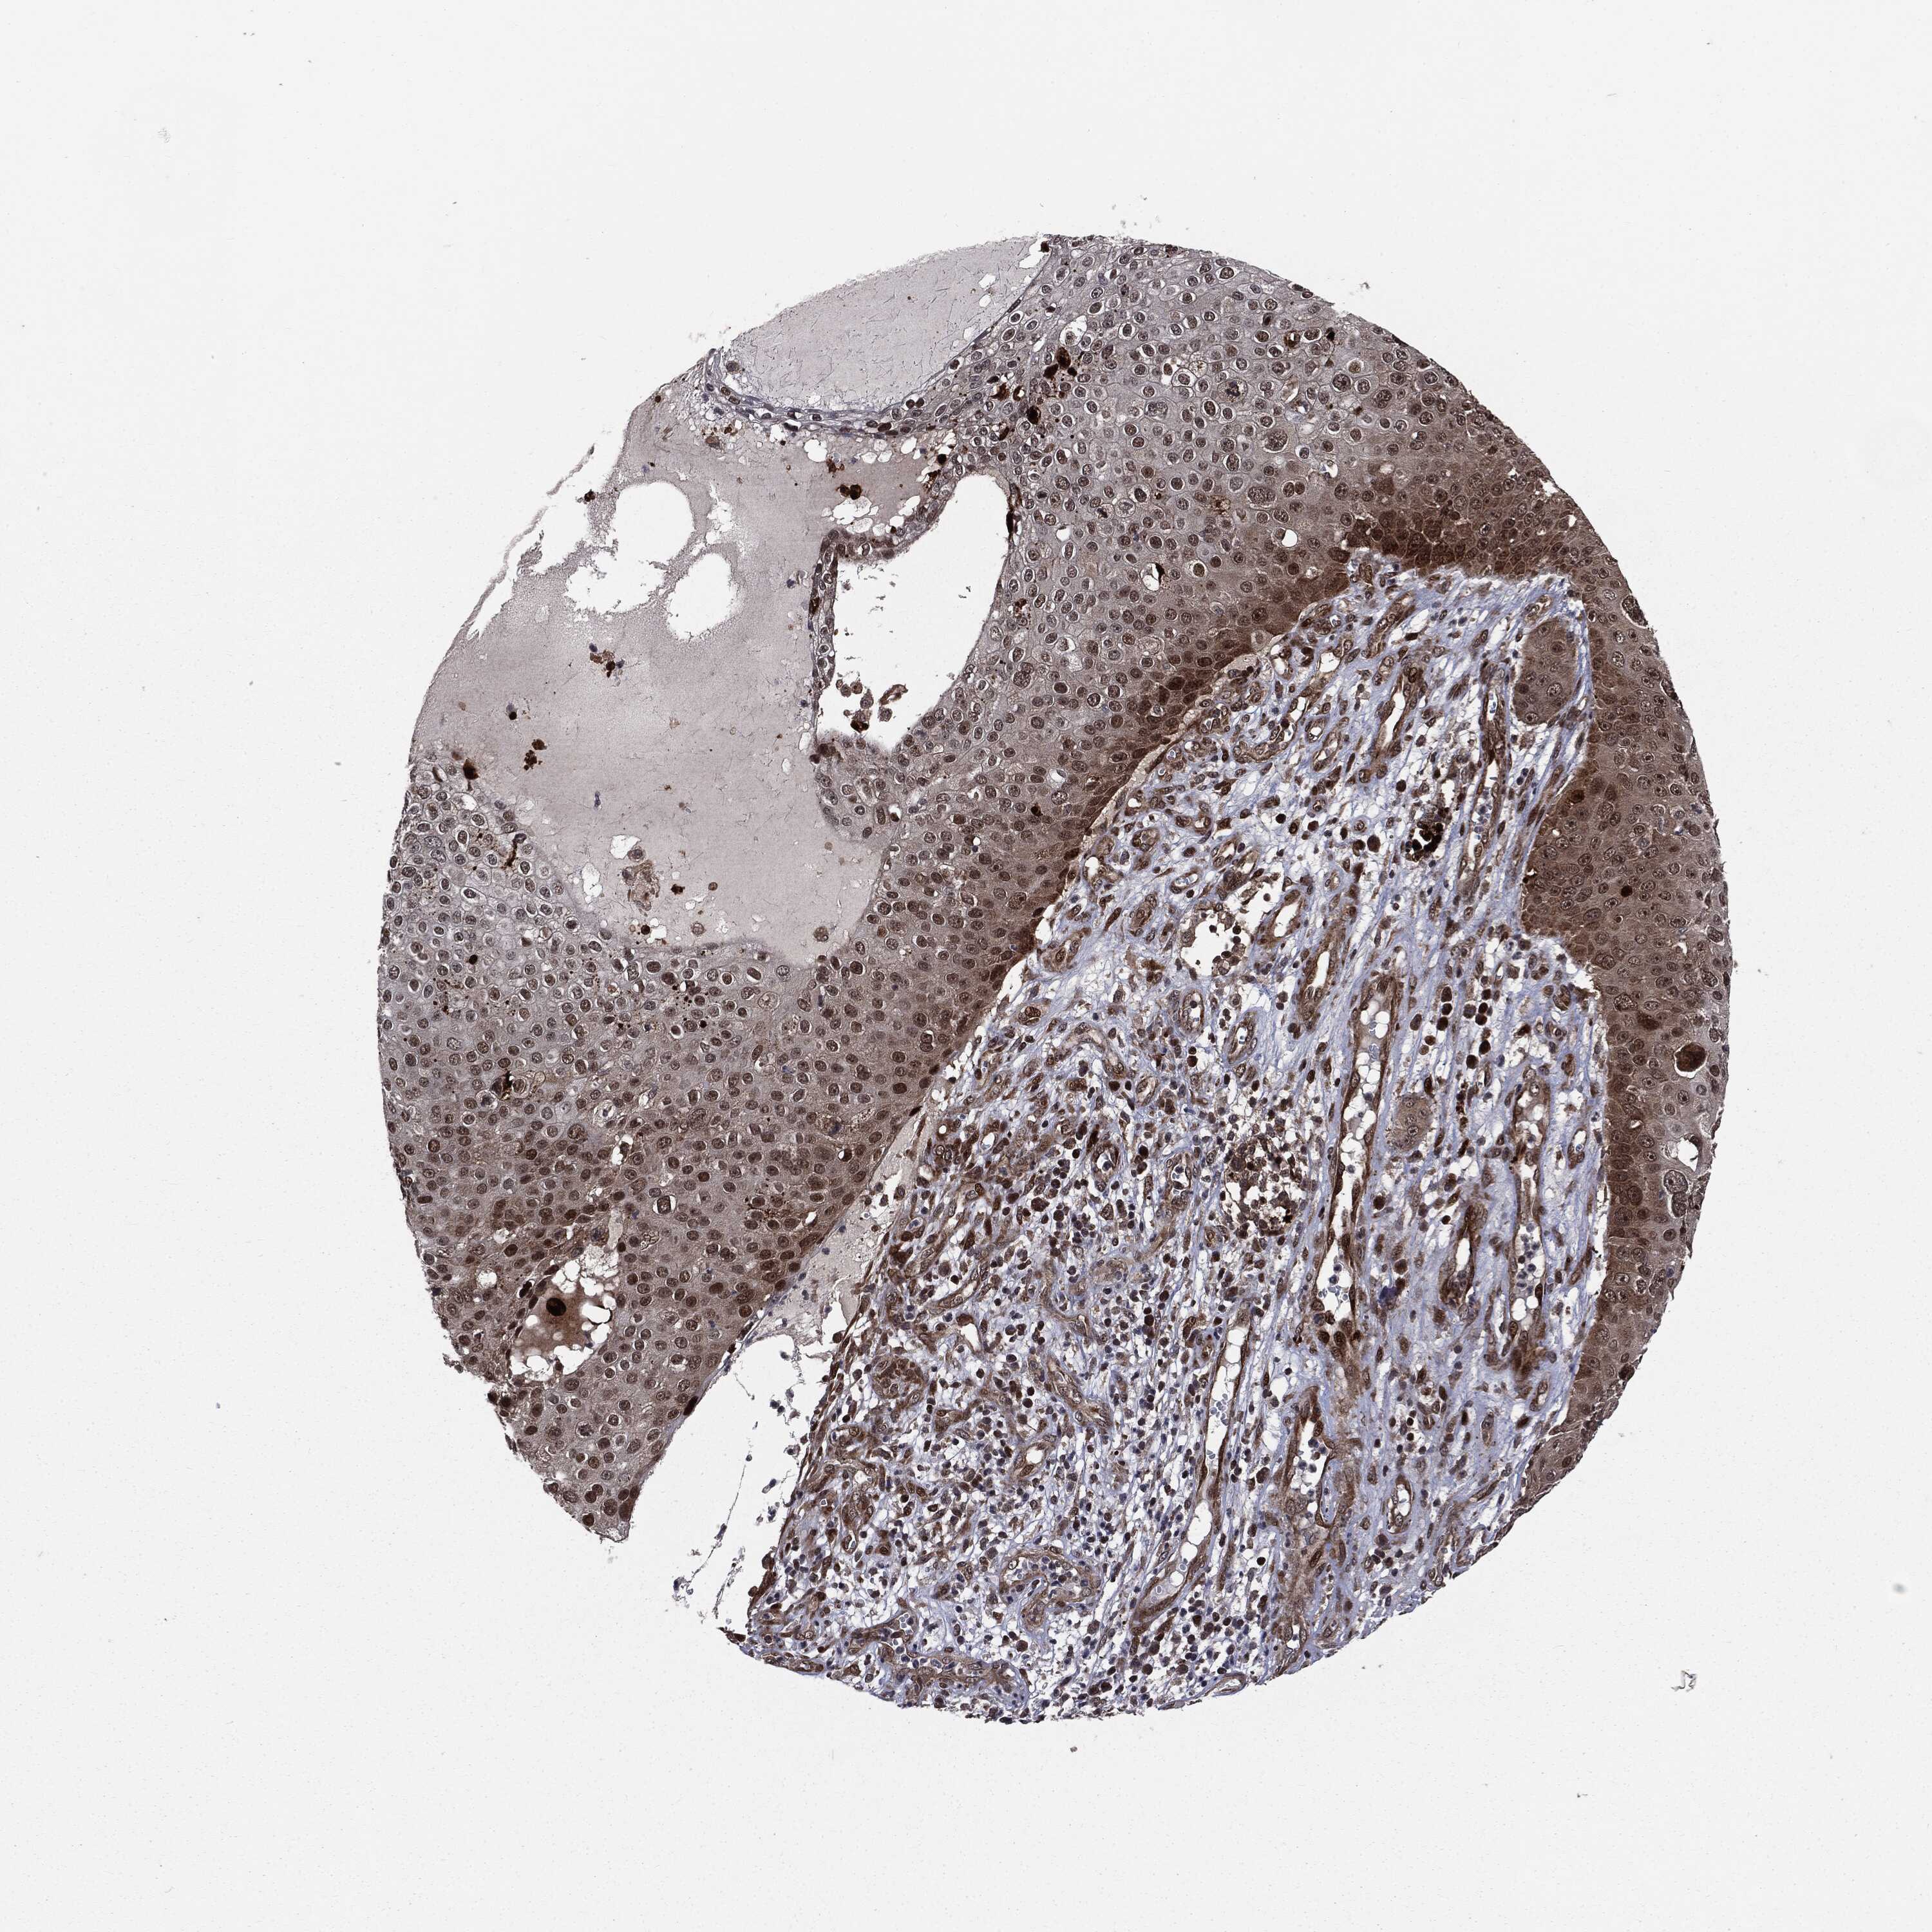

SKIN CANCER - Protein expressioni

A mouse-over function shows sample information and annotation data. Click on an image to view it in a full screen mode. Samples can be filtered based on level of antibody staining by selecting one or several of the following categories: high, medium, low and not detected. The assay and annotation is described here.

Antibody stainingi

Antibody staining in the annotated cell types in the current human tissue is reported as not detected, low, medium, or high, based on conventional immunohistochemistry profiling in selected tissues. This score is based on the combination of the staining intensity and fraction of stained cells.

Each image is clickable and will lead to virtual microscopy that enables deeper exploration of all samples and also displays staining intensity scores, fraction scores and subcellular localization as well as patient and tissue information for each sample.

Antibody CAB080136

Squamous cell carcinoma, NOS